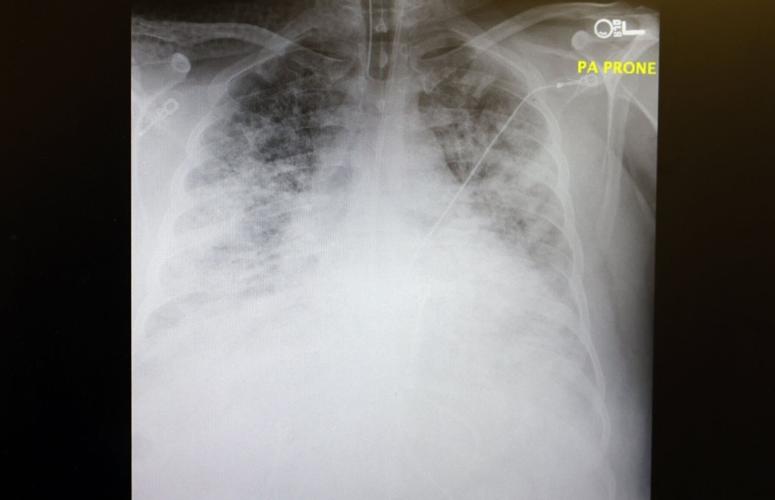

First, it’s now commonplace for previously healthy, younger adults with decades of life expectancy on the line to be among the sickest of the sick. The average age of COVID patients on ventilators at Saint Francis as of Friday was 55 – far lower than when vaccines weren’t yet available.

Second, doctors are now being confronted by critically ill patients begging them for a life-saving vaccine that they cannot administer at such a juncture. Only 9 of the 145 patients, or 6 percent, hospitalized at Saint Francis on Friday were vaccinated.

“I had a patient last week, a 40-year-old whose mom was with him. After we intubated him and put him on the ventilator, I was talking to her about what was going to happen in the next couple of days and that we were going to have to wait and see,” Parker said. “We were going to do everything we could but that I couldn’t promise her he was going to get better.